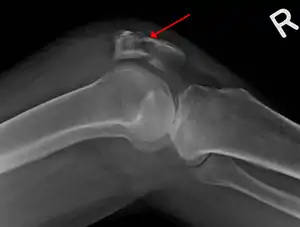

| A fracture of the patella seen on a lateral view | |